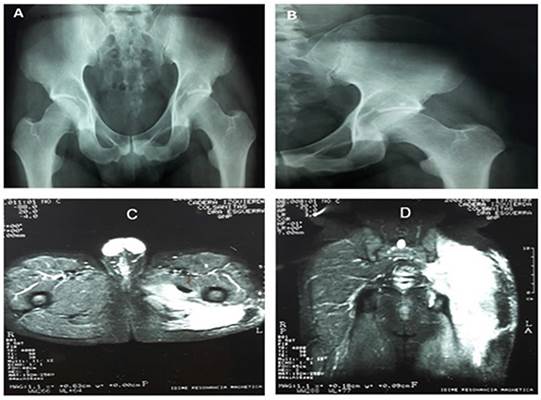

Con ese diagnóstico se remite a una consulta especializada de medicina de rehabilitación y fisiatría donde se revalora al paciente, y en examen físico se observa crecimiento de una tumoración en la región glútea izquierda asociada a pérdida de la movilidad, por lo que se solicita radiografía de pelvis y resonancia magnética nuclear de la zona comprometida. En un control a los 3 meses con ortopedia, el paciente ingresa a la consulta con marcha de Trendelemburg, a la vez que continúa el crecimiento de la masa glútea. Se observaron reportes de la radiografía de pelvis (figura 1 A-B), los cuales son normales, mientras que la resonancia pélvica muestra masa difusa a nivel del glúteo izquierdo, al parecer sin compromiso de órganos vitales. Finalmente se redirige a ortopedia oncológica para valoración, donde deciden programar una resección de la masa más biopsia abierta, en la cual se encuentra una masa en la región glútea, adherida a planos profundos musculares, con una extensión de 30 cm y de crecimiento hacia el muslo, la cual se resecó de manera completa pesando 670 gramos.

La discrepancia diagnóstica es una característica variable, tal cual se dio en este caso, que presenta ciertos hallazgos incidentales en radiografías de pelvis como un flebolito en el borde acetabular izquierdo; estos son normales, aunque pueden indicar la presencia de tumores benignos. Es por esto que para la identificación de tumores de tejidos blandos la toma de imágenes diagnósticas como la tomografía computarizada (TC) y la resonancia nuclear magnética (RNM) permiten obtener claridad diagnóstica 8, 9. La cirugía sigue siendo el tratamiento estándar para la fibromatosis agresiva (AF); sin embargo, el control local y la recidiva son aún el principal obstáculo en su tratamiento. Algunos factores asociados a la recidiva son cirugía con presencia de residuos histológicos (R0), diámetro del tumor (≥ 10 cm) y localización en las extremidades 8-10